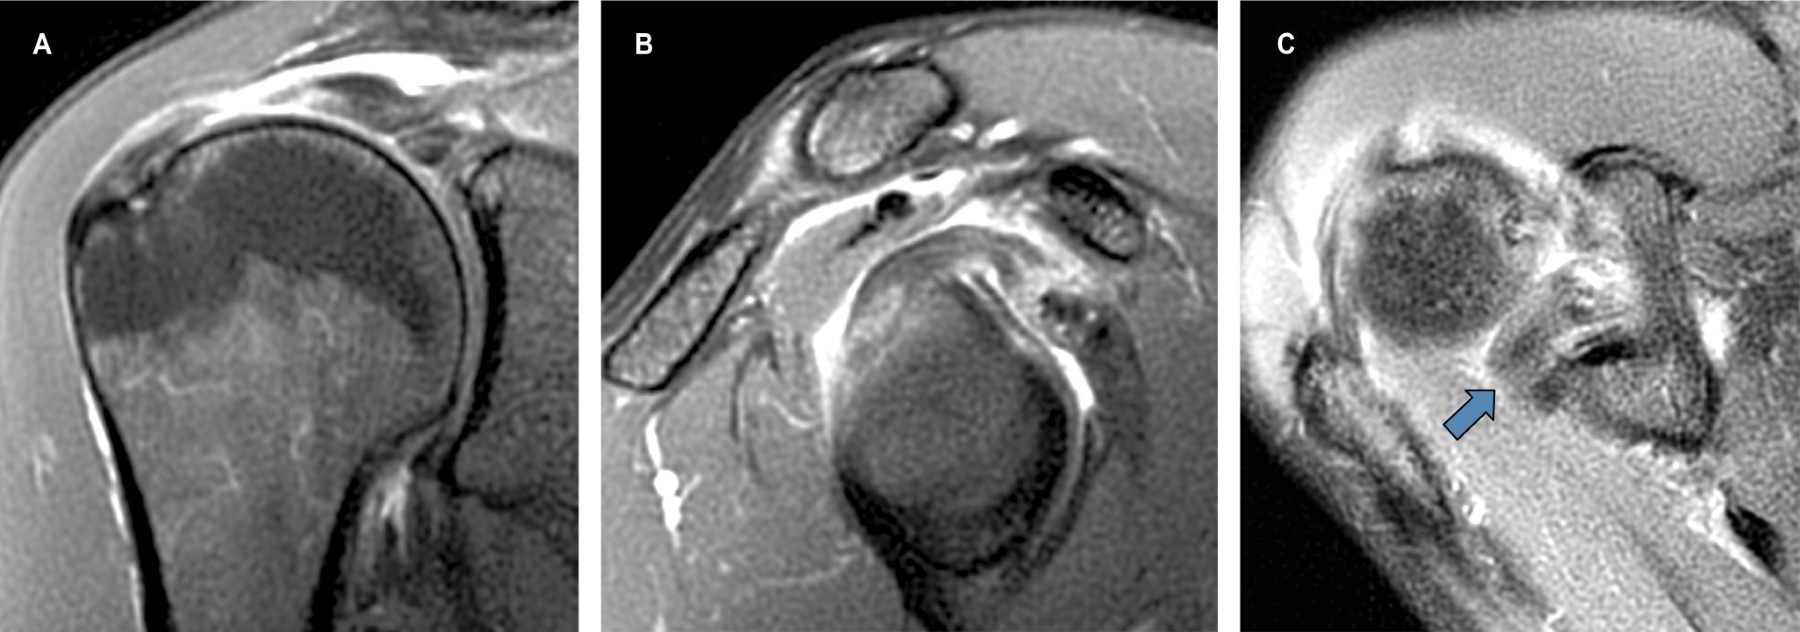

La resonancia magnética evidencia, como diagnóstico principal, una ruptura-avulsión completa de la porción larga del bíceps en su sitio de origen en el tubérculo supraglenoideo, con retracción distal de sus fibras (corredera bicipital vacía) (Figuras 1 y 2). Como hallazgo secundario, se observa tendinitis con ruptura parcial intrasustancia y de la unión miotendinosa del supraespinoso (Figura 3). Estos hallazgos explican de forma precisa la correlación clínica e imagenológica descrita en la solicitud, y demuestran la alta sensibilidad y especificidad de la resonancia magnética de hombro para la detección detallada de lesiones musculoesqueléticas.

Figura 2